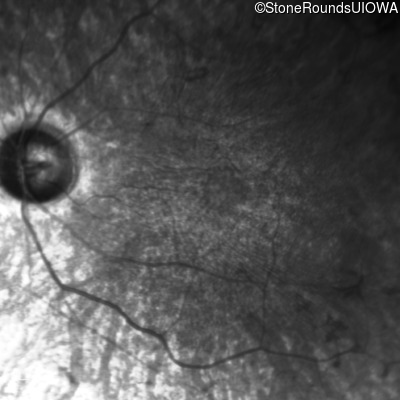

This 21 year old man first had difficulty seeing the blackboard in the 5th grade. Two years later he began having difficulty seeing in dim light. In high school he was approximately 50 pounds overweight, but was able to lose that weight with a strict diet.

| Bardet Biedl Syndrome | BBS1 | Met390Arg ATG>AGG | Arg277Lys AG(G)>AA(G) | AR |